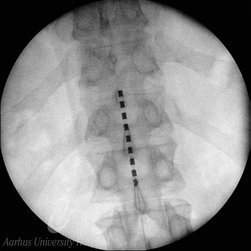

Spinal Cord Stimulation (SCS)

See Pain Research above.

We have worked clinically and scientifically with spinal cord stimulation (SCS) for chronic, neuropathic pain for more than 15 years. The last 5 years we have also worked with occipital nerve stimulation (ONS) for chronic cluster headache (Horton’s Headache), and with peripheral nerve stimulation (PNS) for painful mononeuropathies.

Our research has been focused on investigating predictors for treatment outcome, mechanisms of action, cost/benefit modeling, safety in pregnancy and outcome parameters. The Neurizon Neuromodulation Database, founded in 2012, forms the cornerstone of our research and registers all patients treated with neuromodulation for chronic pain in Western Denmark.

Cense group have extensive experience with the use of various imaging techniques in neuroscience-related research using large animals (pigs and minipigs) under anesthesia. The size of the pig/minipig brain allows us to use standard clinical imaging modalities. Routinely, we are using anatomical and stereotactic MRI in the planning of the surgeries and evaluation of their outcome (verification of the electrode placement, effects of the electrocoagulation etc.) as well as in the long term studies (like the evaluation of the effect of radiation on the nervous tissue). Designed by our group MRI compatible localizer box and stereotactic frame allows us to precise targeting of various minipig brain structure. We have also experience with ex-vivo, post mortem MRI and fiber reconstruction. Other imaging techniques used by us include computed tomography (CT), positron emission tomography (PET - used in the analysis of the brain activity or dopaminergic neurotransmission studies) or X-ray imaging (fluoroscopy). Our group have established close collaboration with the PET Centre and Center of Functionally Integrative Neuroscience (CFIN) MRI group, localized in the Aarhus University Hospital, allowing us to test various imaging paradigms.